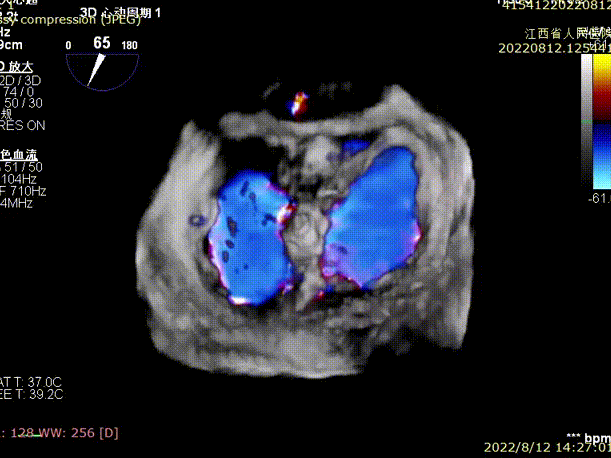

手术于全麻下进行,采用经典股静脉房间隔途径,房间隔穿刺后置入24F导引导管及二尖瓣夹输送系统,在TEE引导下准确植入一枚二尖瓣夹至A2/P2区,瓣膜夹位置稳定,植入后反流下降至1+,二尖瓣跨瓣平均压力阶差1mmHg,双孔化形成,遂移除器械输送系统。超声心动图评估瓣膜夹位置和功能良好,瓣膜夹活动度低,手术顺利完成。

术后TEE显示,二尖瓣夹植入后反流减少